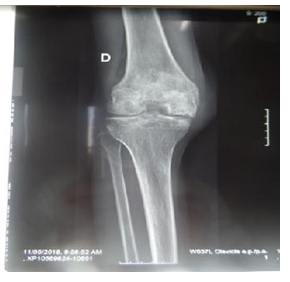

Hemophilia A was dominant in 63.33% of cases and was severe in 90% of cases. More than half of the hemophilia patients involved (n = 19.64%) had hemarthrosis between 3 and 5 times per year. Haemarthrosis was localized most often (n = 12.40%) at the knee level and without any other location (Figure 1). The locations at the elbow (Figure 2) and the ankle (Figure 3 & 4) were less frequent.

Figure 2 Hemarthrosis in the left elbow.

Forty percent of our patients had knee osteoarthritis. Haemarthrosis has been described mainly in the knees according to Nouffissa20 and his collaborators. According to Lobet and colleagues,18 hemarthrosis affects mostly the knees and elbows in subjects over 30 years of age, whereas they mainly affect the ankles in the very young. Diop and colleagues21 reported that hemarthrosis is localized mainly in the knee, then the elbow and ankle. The susceptibility of these joints to hemarthrosis is explained by the fact that they have only one plane of mobility and that any stress outside this plane can lead to a capsulo-synovial elongation source of haemorrhage. In this study, we reported the frequent location of hemarthrosis in the knee. Thus, our data are in good agreement with those of the literature.

70% of patients had knee arthropathy. The study conducted by Windyga10 reported mainly the prevalence of arthropathy in the knee in 92 severe hemophiliacs. In contrast, Strauss and colleagues14 reported 21 cases of hemophiliacs with arthropathy in the elbow. This could be explained by the anatomical complexity of the elbow joint. Utukuri et al.22 also conducted 26 cases of elbow arthropathy in 2005 in London.